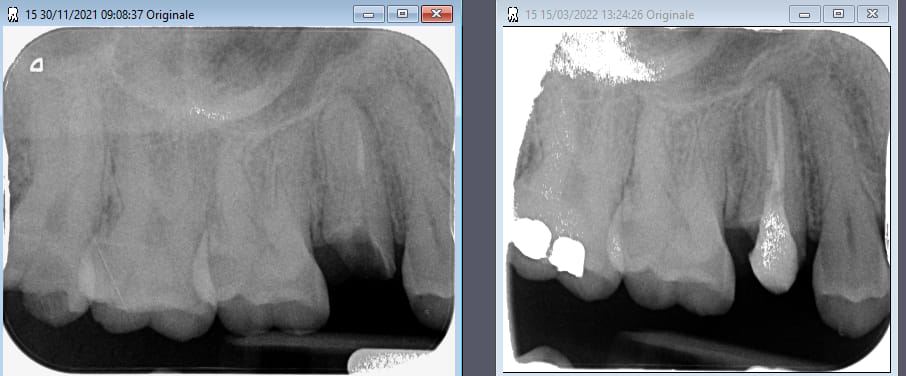

Depuis plus de 3 ans j'utilise le AH plus jet de chez sirona + macspadden... (ciment résine epoxy)

c'est très pratique d'usage, l'ergonomie est excellente et j'ai pas de sensibilité post op meme en cas de puff.

Des études que j'ai lu, les ciments epoxy sont tres efficaces, peu de rétractation de prise pas d hydrolyse et biocompatibilité bonne.

Et excellente étanchéité.

L'AH+ est cependant le matériau le plus radio opaque du marché ce qui rassure bien sur les obturations.

PS: joli l'endo de la 6